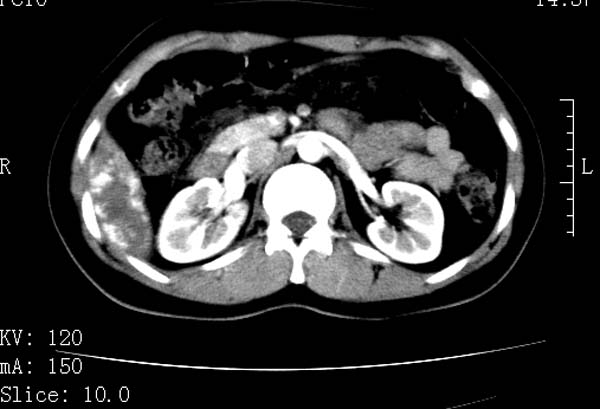

标题: CT22086:女44岁 肝右叶占位增强示巨大血管瘤,门脉期发现小 [打印本页]

标题: CT22086:女44岁 肝右叶占位增强示巨大血管瘤,门脉期发现小

支持肝右叶血管瘤诊断。 小病灶亦考虑血管瘤改变。温习一下:

肝海绵状血管瘤ct平扫常呈均匀低密度,与邻近血管密度相仿。在脂肪肝背景下可呈相对高密度。在增强扫描时,一般早期(动脉期)呈周边结节状或弧形强化,其密度与同层面的血管密度相仿,随着时间延迟向中央渐进性充填,注药后5~7分钟,逐渐扩大至全瘤强化,强化密度逐渐降至稍高于或等于正常肝脏。大的血管瘤往往中央有星形、大的低密度区,可以为纤维化或囊性变所致,纤维化成分可在延迟2 o分钟时完全充填,呈等密度,但囊变区则不会强化。不典型ct表现常见于≤3 cm的小血管瘤。小的血管瘤可以在动脉期即呈全部致密的均匀强化,不呈典型的周边结节状强化表现,但其密度往往较高,与主动脉相仿,在延迟期呈高或等密度。其他不典型的ct表现有:增强扫描强化不明显,呈点状较轻程度的强化,充填慢,可能与供血动脉较细和较大的血管间隙有关以及中央先强化等。

延迟扫描三个病灶都呈等密度改变。肝多发血管瘤,较典型。